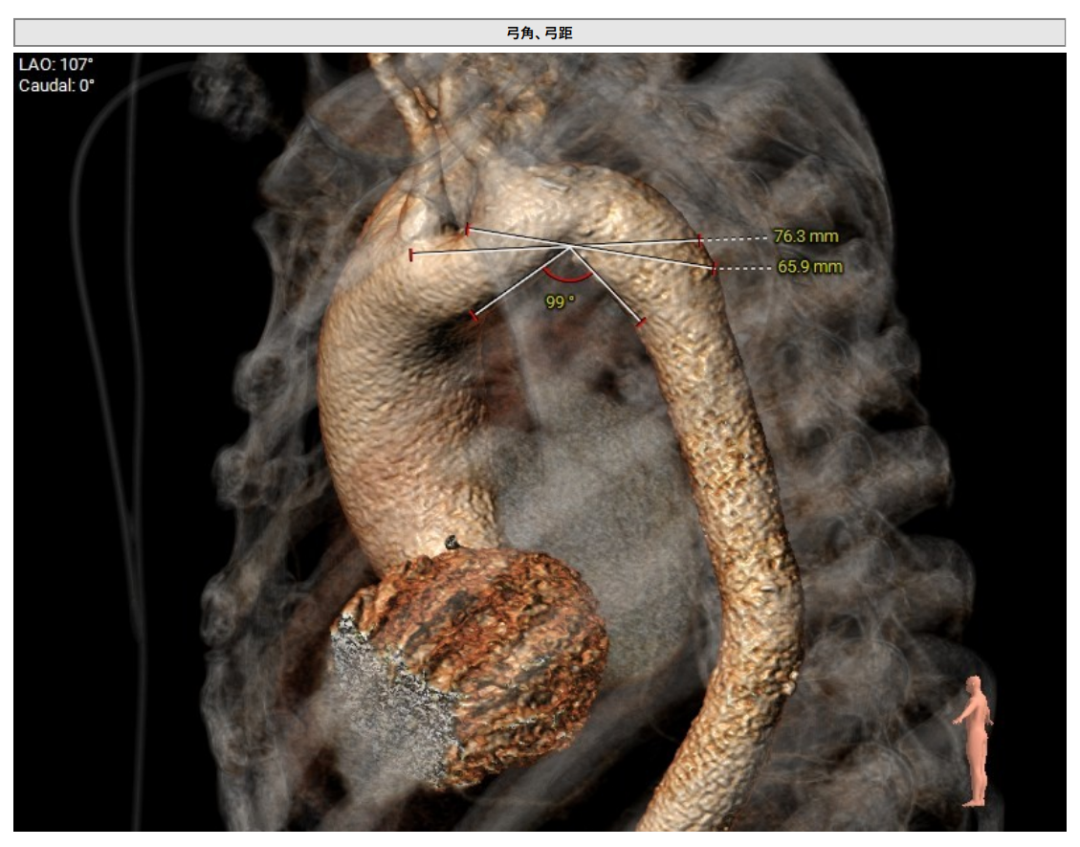

术前CT(上下滑动查看更多图片)

术中造影